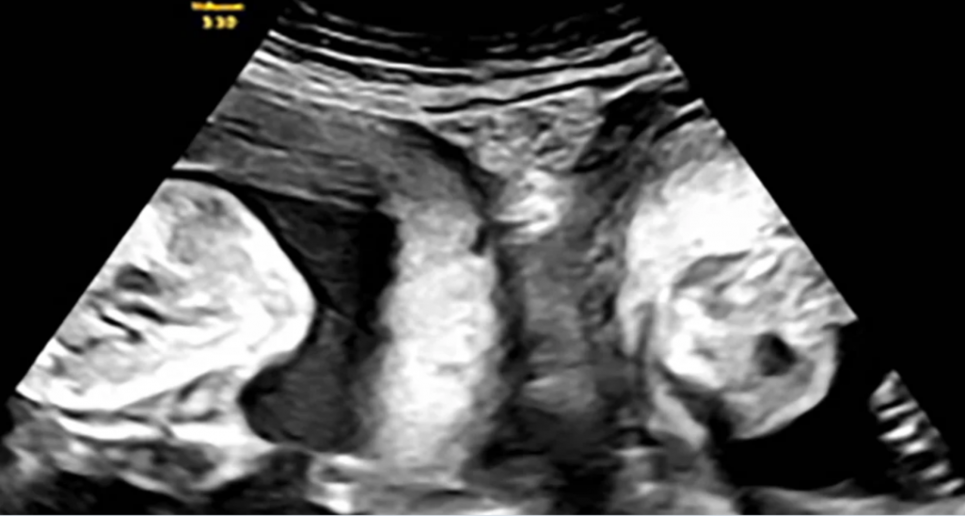

Попередня вагітність пані Лі закінчилася викиднем. Але в січні жінка завагітніла знову й під час раннього УЗД виявила, що чекає не одну дитину, а двійню — по одній дитині в кожній матці.